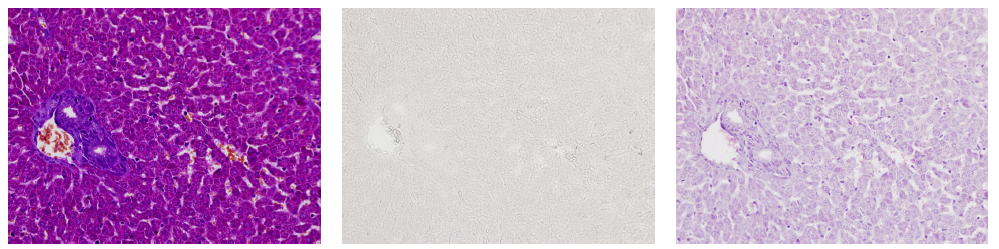

MT染色脱色(MT→脱色→HE)

小鼠肝脏